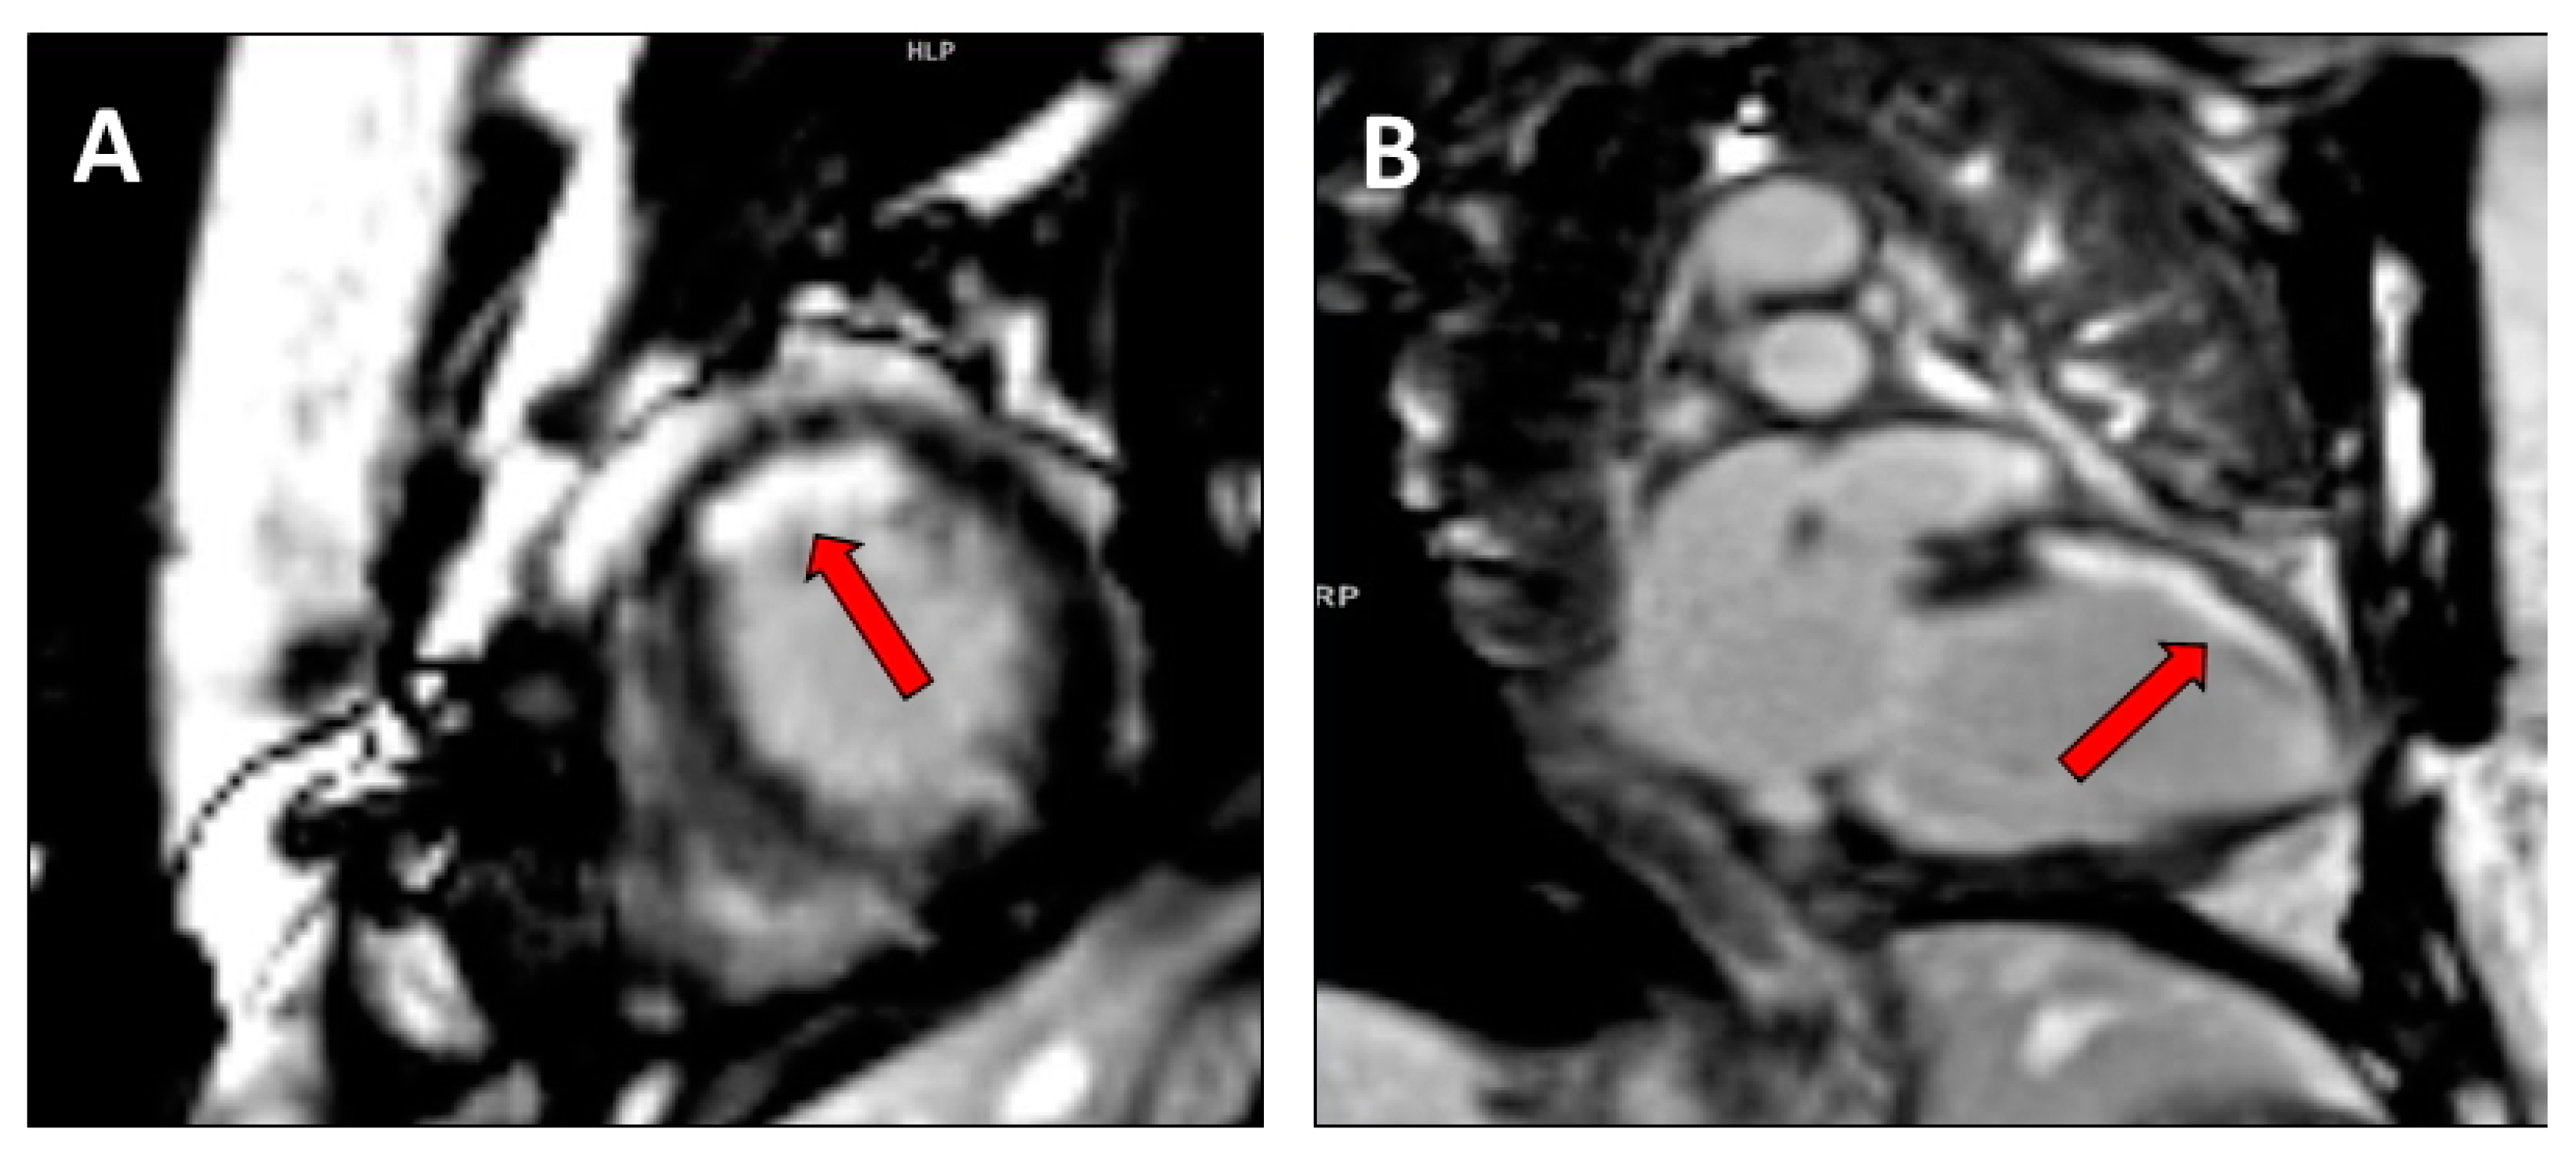

CMR with late gadolinium enhancement can provide information on the entity and localization of scarred myocardium with high accuracy [12]. Figure 3 and Figure 4 show examples of CMR with late gadolinium enhancement imaging for scar identification in myocardial infarction. Leyva et al. [30] investigated the use of late gadolinium CMR before CRT implantation, showing that pacing LV scarred myocardium was associated with high risk of cardiovascular death, hospitalizations for heart failure, and death from any causes. Conversely, in the study by Taylor et al. [31], LV lead positioning over non-scarred LV segments, as assessed by late gadolinium enhancement CMR, was associated with better LV reverse remodelling and clinical outcomes at follow-up.

Figure 4.

Cardiac magnetic resonance with LGE imaging in a mid/apical subendocardial myocardial infarction (red arrow) in (A). short axis mid ventricular view and (B). two chamber view.